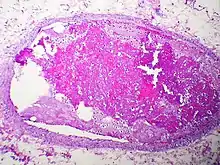

Embolism by other materials is rare. Septic embolism happens when a purulent tissue (pus-containing tissue) is dislodged from its original focus. Tissue embolism is a near-equivalent to cancer metastasis, which happens when cancer tissue infiltrates blood vessels, and small fragments of them are released into the blood stream. Foreign-body embolism happens when exogenous—and only exogenous—materials such as talc enter the blood stream and cause occlusion or obstruction of blood circulation. Bullet embolism occurs in approximately 0.3% cases of gunshot wounds.[8] Amniotic-fluid embolism is a rare complication of childbirth.

Septic emboli may also be a contributor to spreading infection through the bloodstream to other tissues.